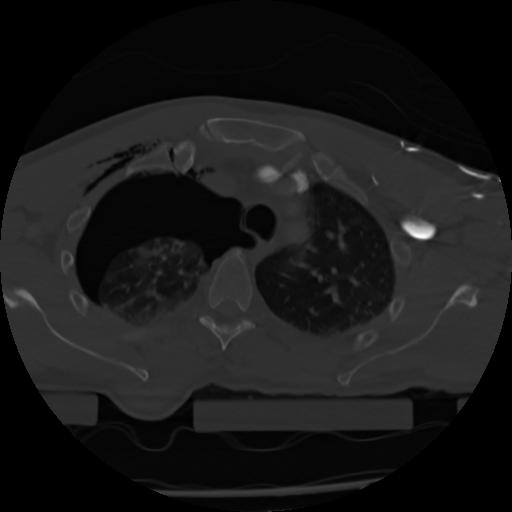

21 ANGIO,CE,Axial,3.0,ANGIO,,